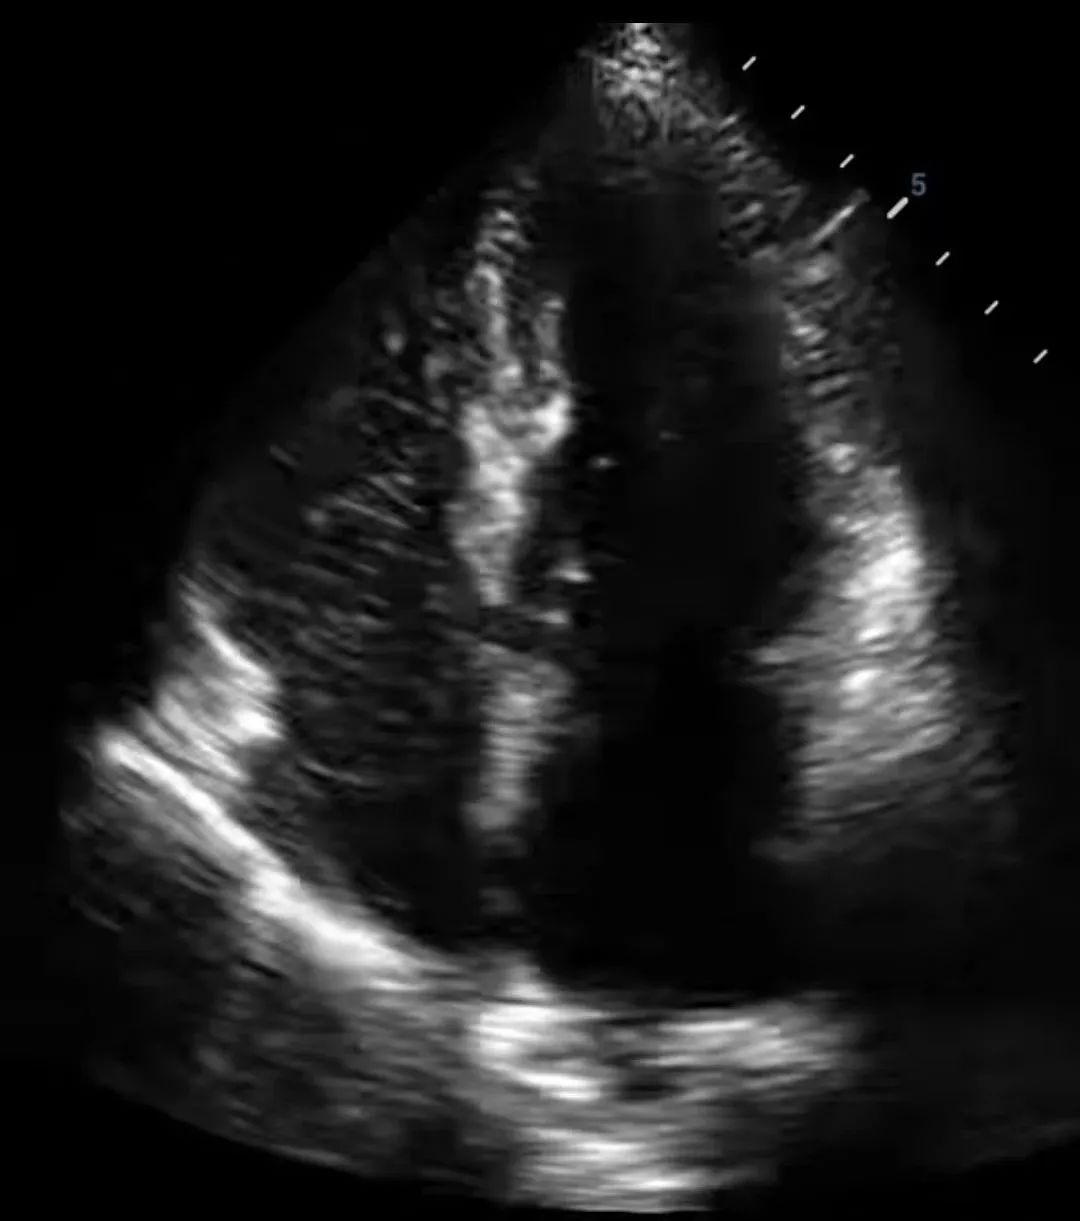

随后,秦姐到超声科做了右心声学造影检查,发现有微气泡由右心进入左心,即心脏发泡试验阳性。排除其他疾病后,医生为其行经皮卵圆孔封堵术。术后头痛症状消失,为她解决了多年的困扰。

大部分PFO患者做经胸超声心动图时是无法看到房水平分流信号,因此不能诊断,需要借助右心声学造影来进行诊断。

右心声学造影技术,是经外周静脉注入造影剂,根据造影剂气泡的显影情况来协助诊断的检查方法。造影剂气泡直径>10um,平均约15um,按照正常途径不能通过肺毛细血管网,不进入左心系统。因此可以根据造影剂气泡显影顺序、途径和时间对某些结构和血流异常做出诊断。